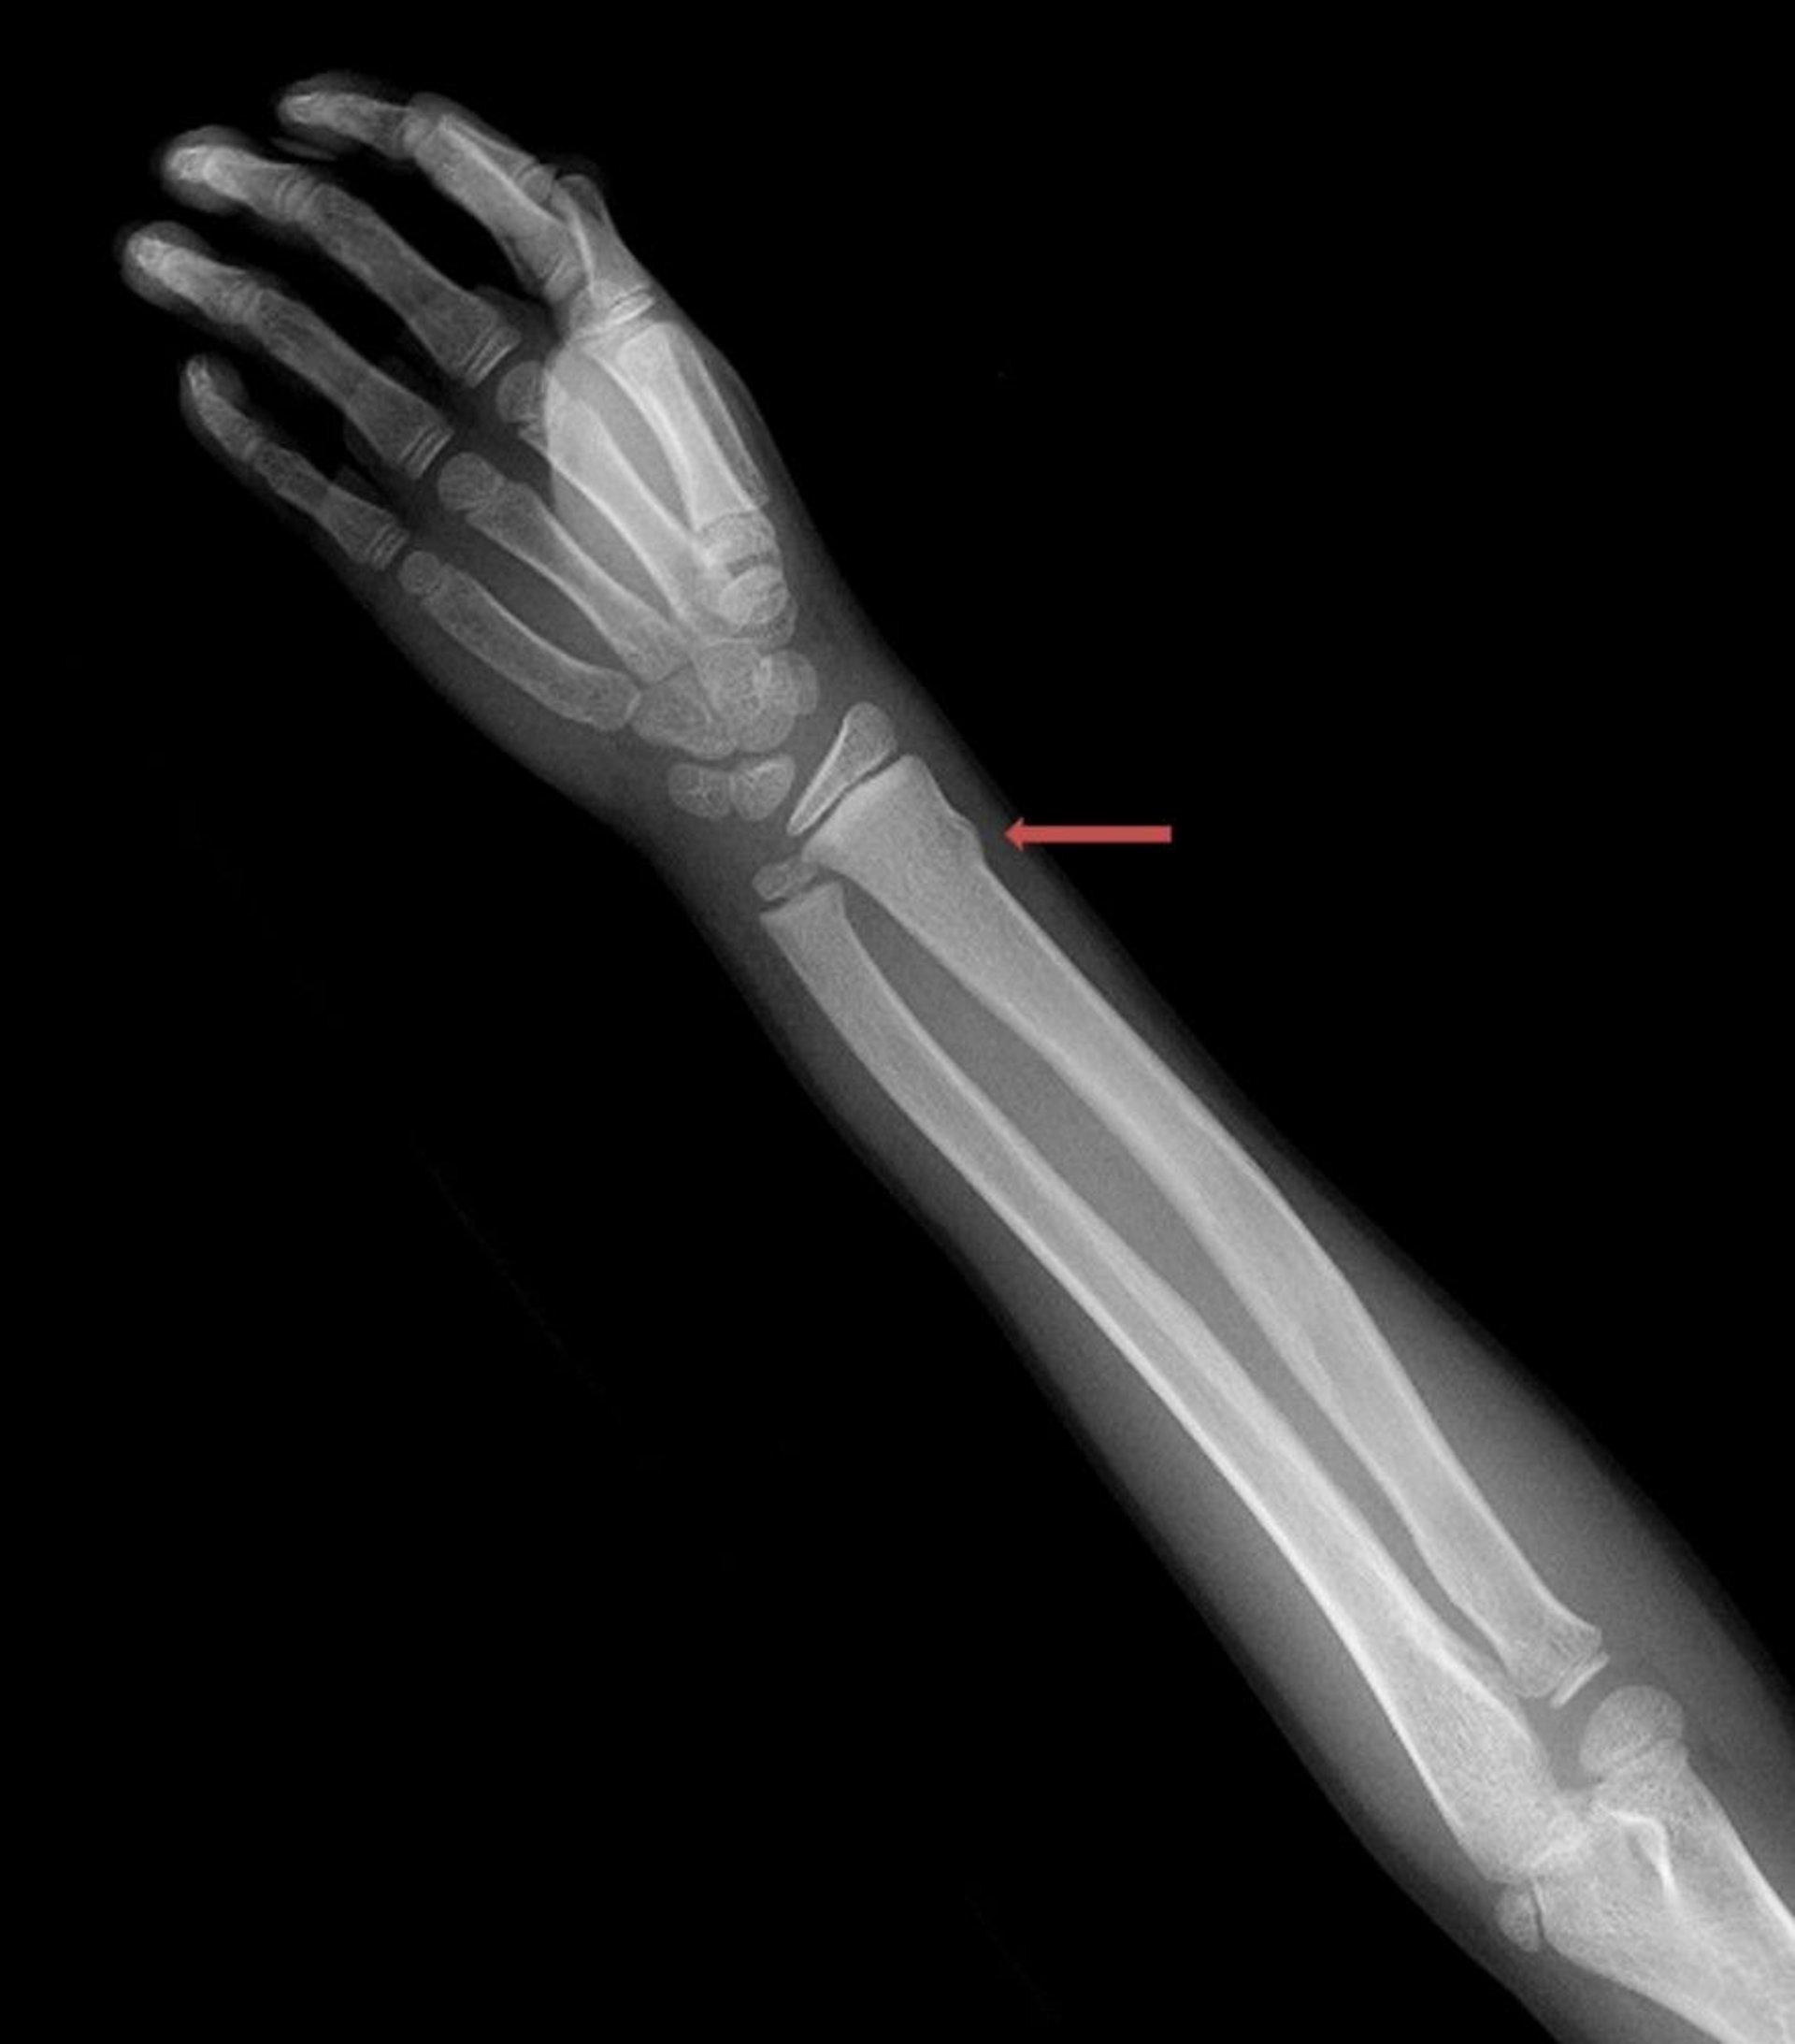

Torus Wrist Fracture

This torus fracture of the distal radius is visible only as a slight irregularity of the bone cortex.